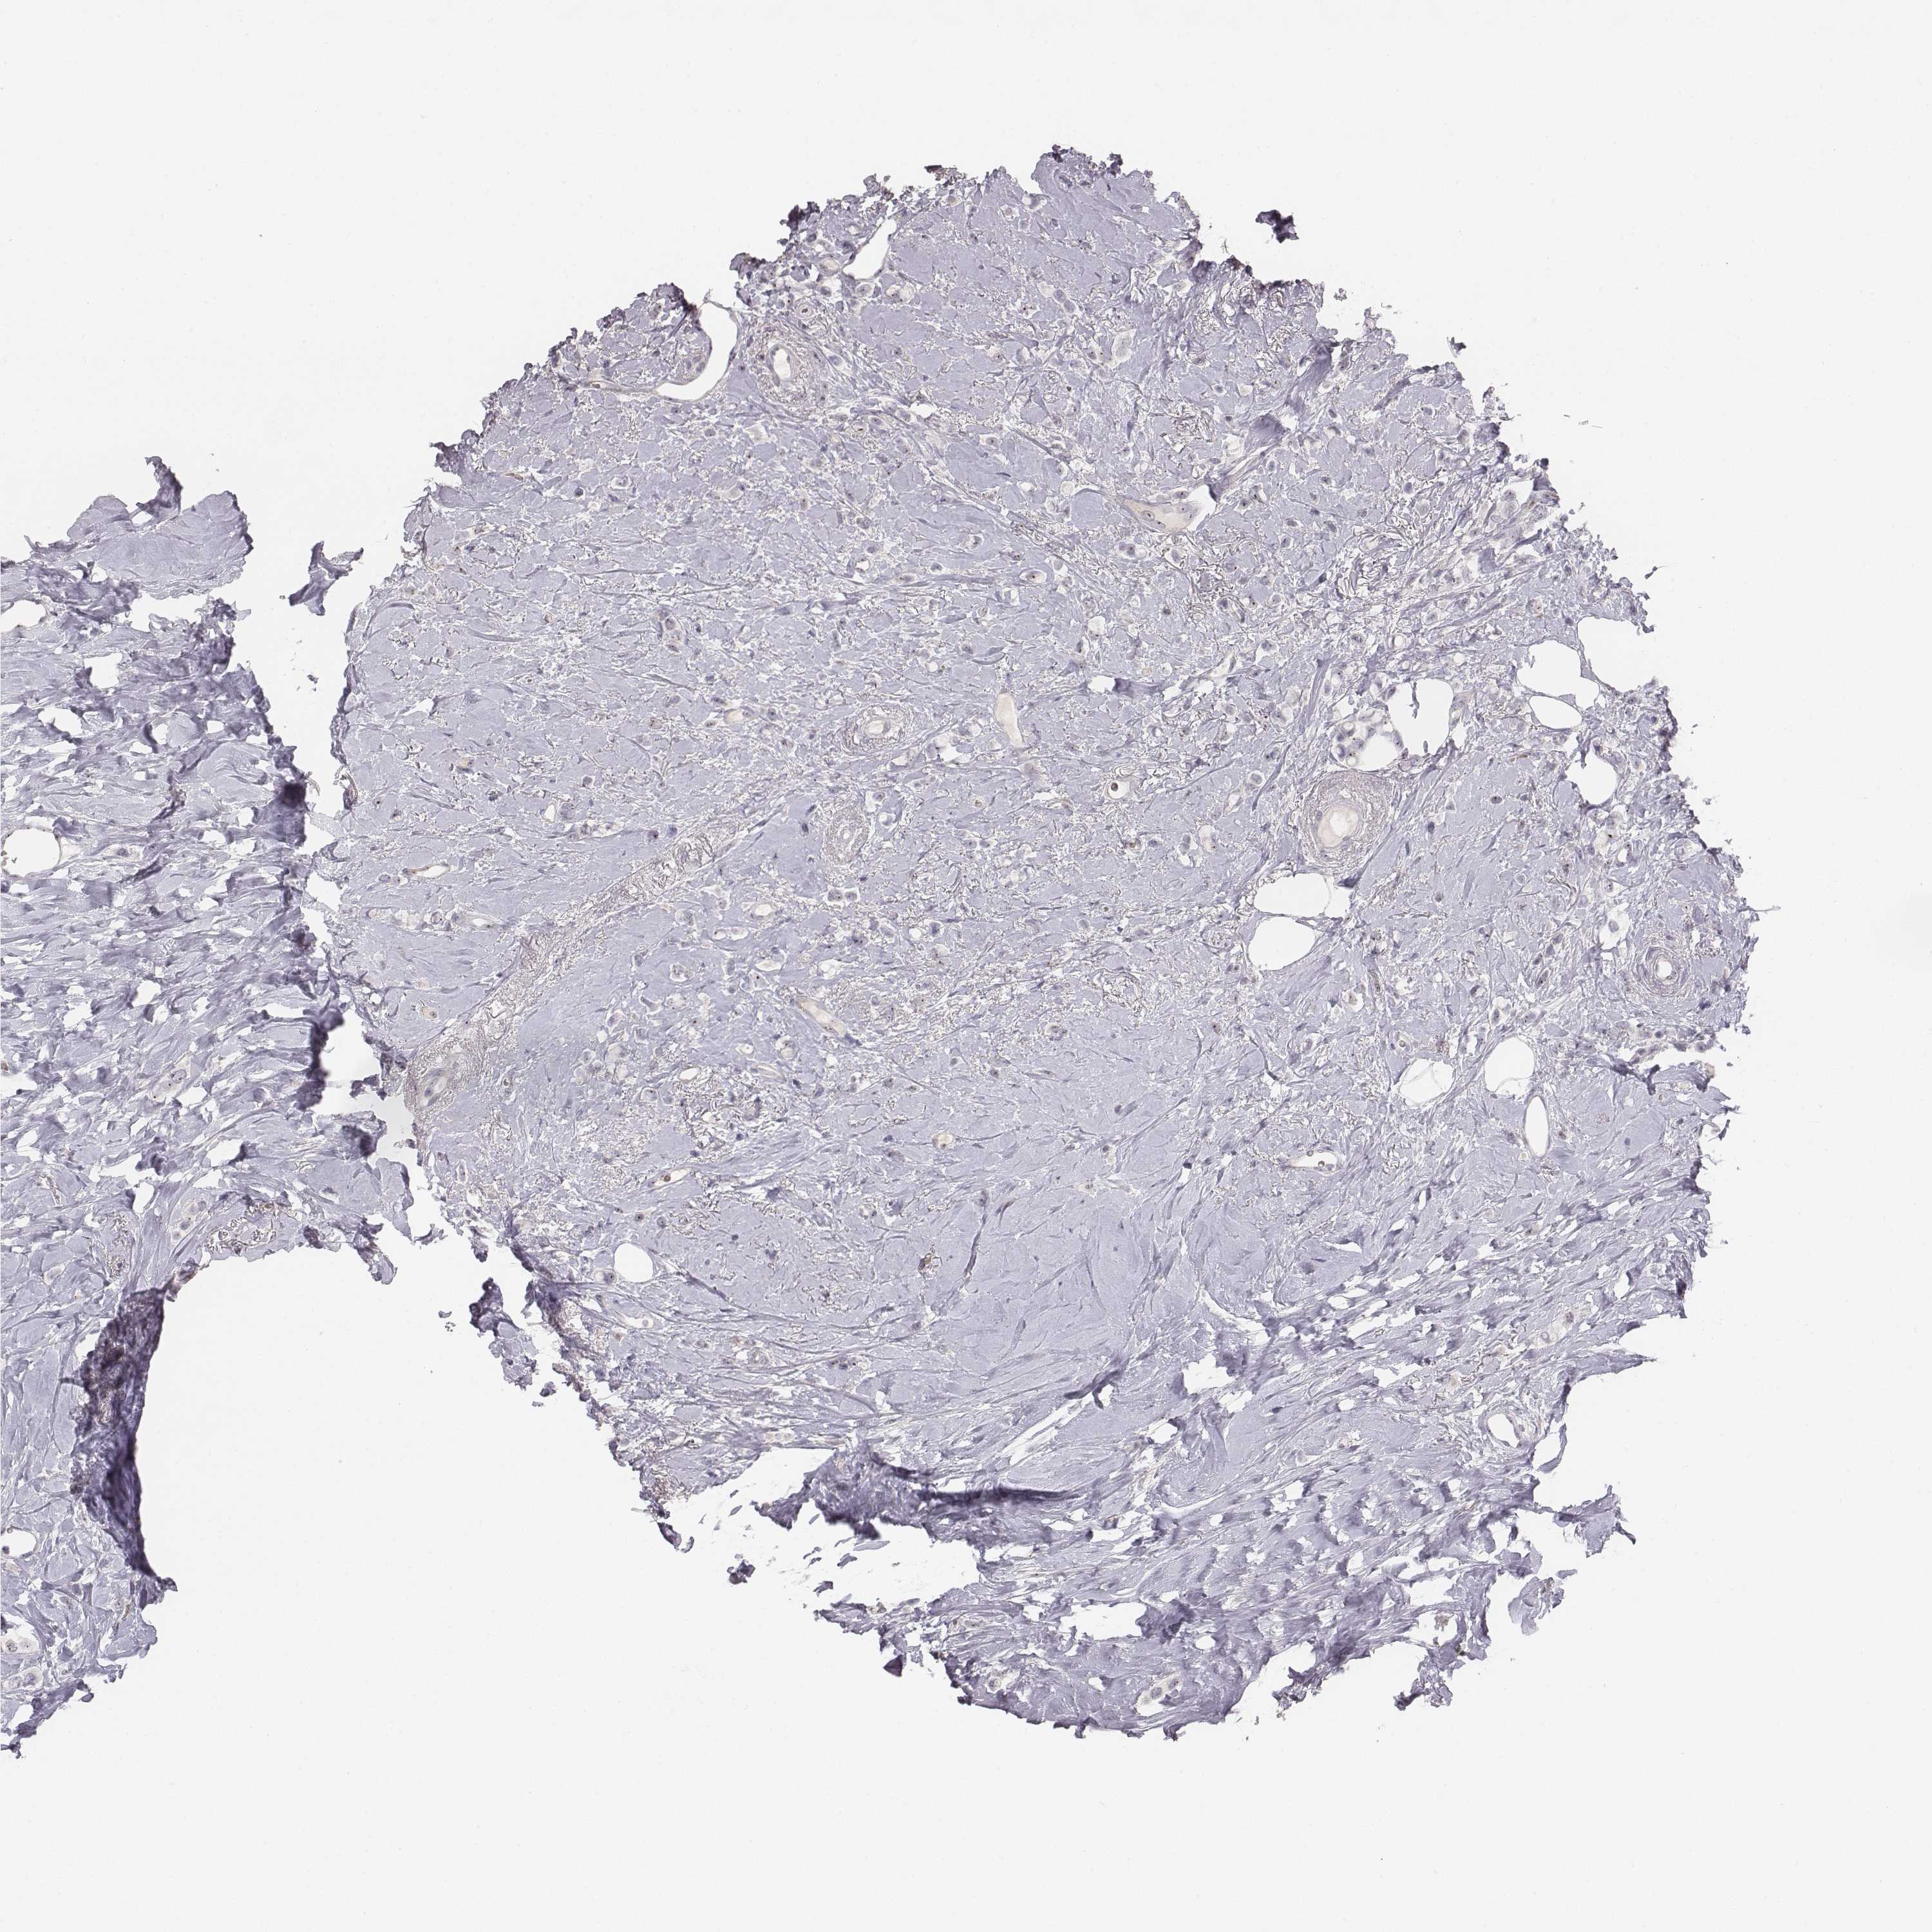

CANCER BREAST CANCER Show tissue menu

BRCA TCGA BRCA VALIDATION PROTEIN EXPRESSION

Breast cancer

Human cancer